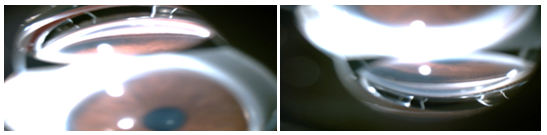

A 11 year old boy of Indian origin presented to us for the first time for reevaluation of his refractive status. He was previously diagnosed at various ophthalmic centres to have compound regular myopic astigmatism and had been prescribed glasses since five years of age. At presentation, his best corrected visual acuity in right eye was 6/9 with -3DS/-3.00 D Cyl at 20 degrees and in the left eye 6/6 with -3DS/-3.00 D Cyl at 160degrees. There was diffuse pigment dispersion on the corneal endothelium of both eyes. Anterior chamber was deep with slit like transillumination defects in both eyes in the mid peripheral iris. Phacodonesis was present in both eyes. On dilatation, posterior subcapsular cataract with subluxation of the lens for 2 clock hours in the right eye and 6-8 clock hours in the left eye was seen (Figure1A). Posterior capsule revealed a pigmented line superiorly in both eyes (Zentmeyers Line) (Figure1B).

Figure 1A Subluxation of lens (Right and Left eye).

Figure 1B Pigmentation over posterior lens capsule.